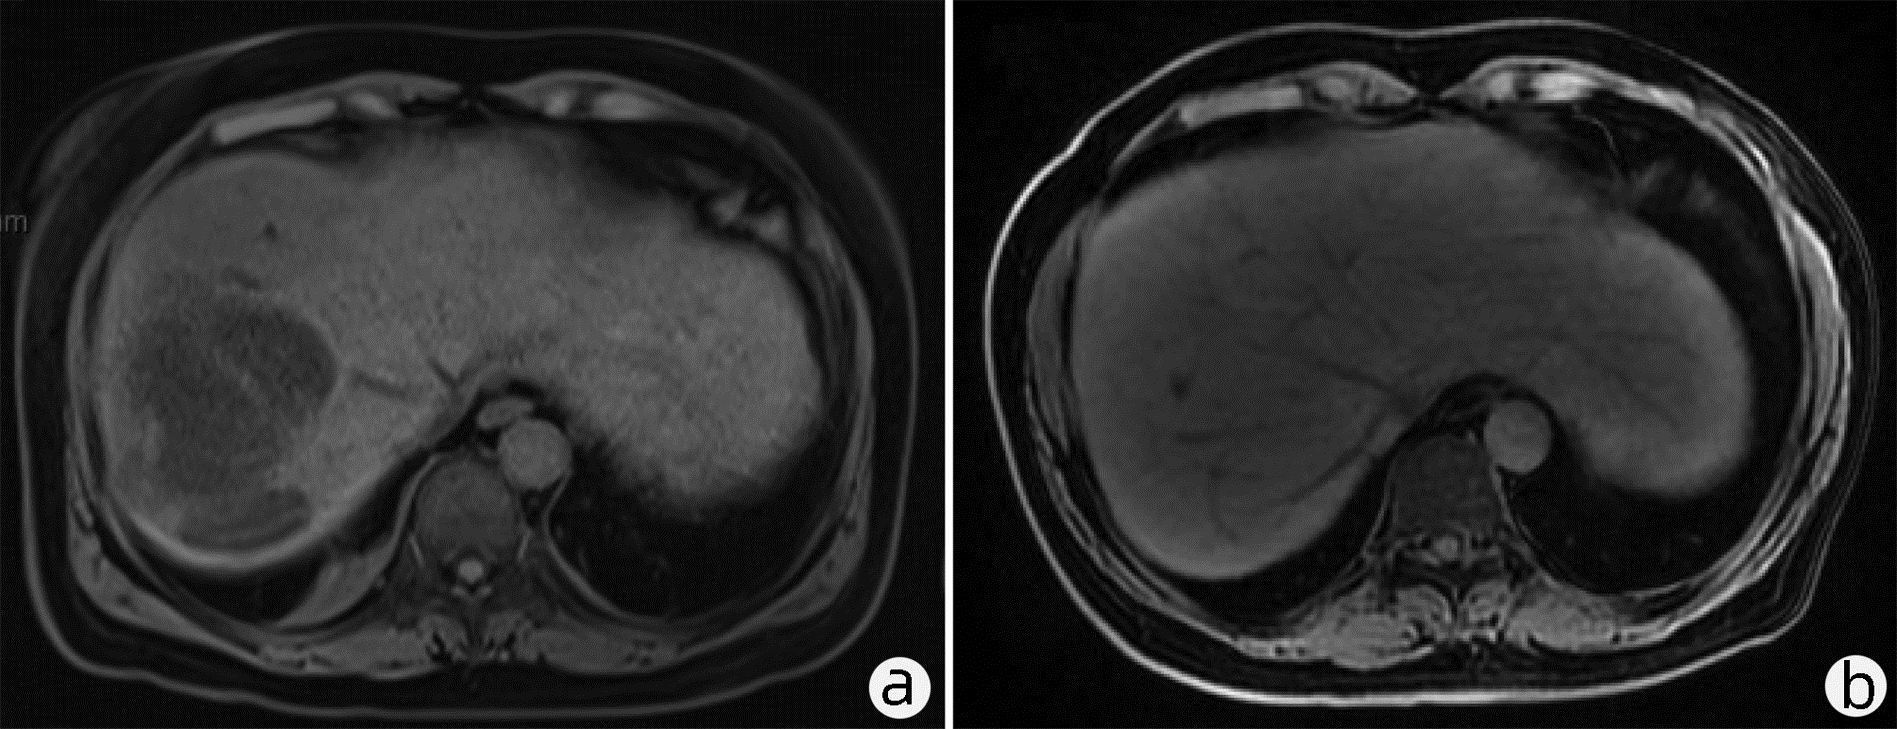

肝窦阻塞综合征成功诊治1例报告

耿雯倩, 朱浩, 杨鑫, 李婉玉, 许芳, 蔡艳俊, 高普均

2023, 39(2): 397-400. DOI: 10.3969/j.issn.1001-5256.2023.02.023

摘要(1461) HTML (477) PDF (2418KB)(136)

摘要: